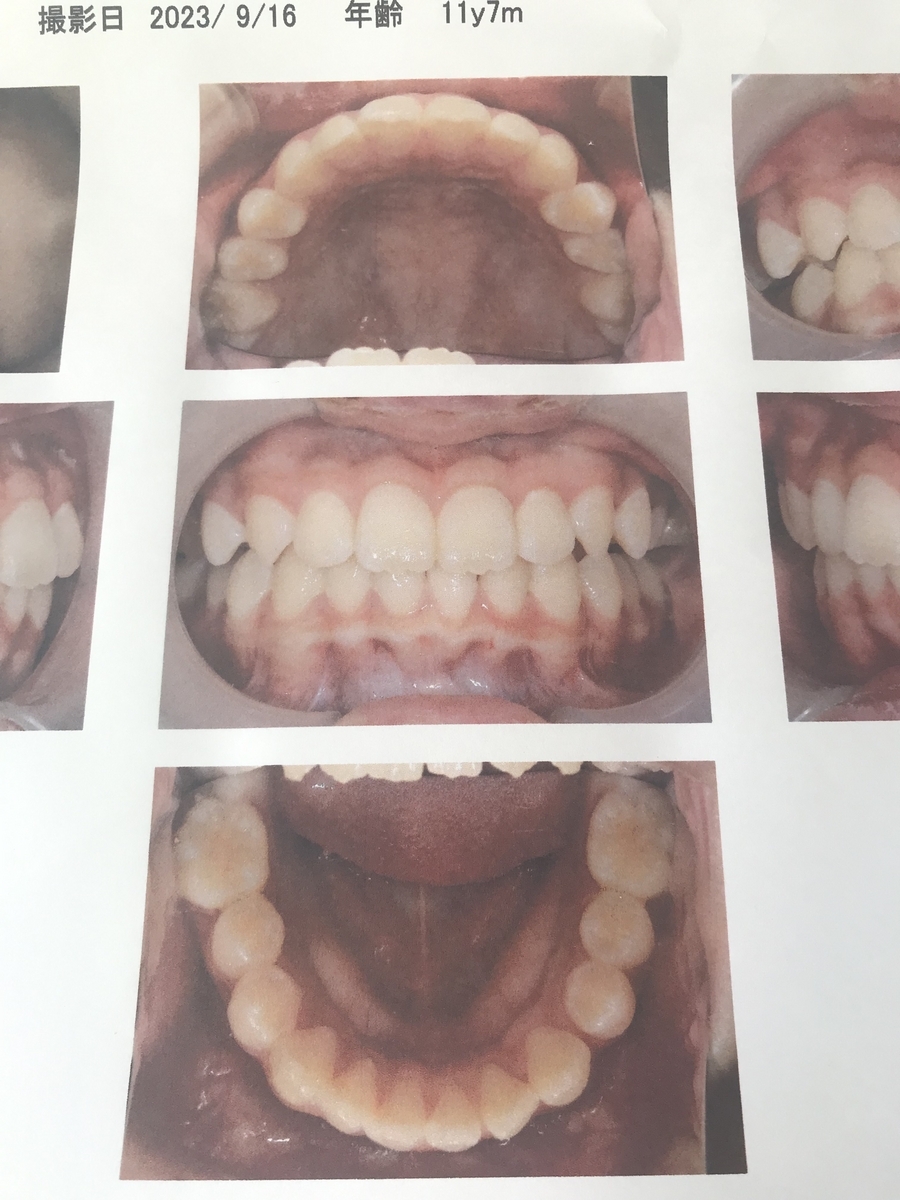

2023年9月(6年生)

一番奥の歯意外生え変わりました。とてもきれいに揃いましたね!がんばりました(泣)